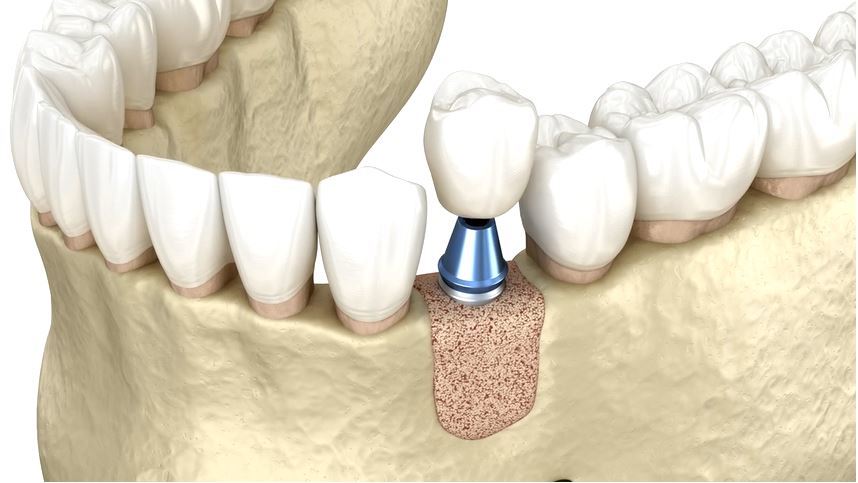

2.پیوند استخوان هم زمان با کاشت ایمپلنت

اگر میزان کمبود استخوان زیاد نباشد، می توان در همان جلسه ای که ایمپلنت کار گذاشته می شود، نقایص کوچک اطراف ایمپلنت را با گرافت (اغلب آلو یا زنوگرافت) و غشای مناسب پوشش داد.

در این حالت، پیوند استخوان پیش از کاشت ایمپلنت به صورت محدود و در همان زمان جراحی اصلی انجام می شود.

۳. پیوند استخوان مرحله ای قبل از ایمپلنت

در تحلیل های شدید استخوان، ابتدا باید حجم استخوان مجدد ساخته شود، سپس چند ماه بعد ایمپلنت کاشته شود. در این پروتکل:

- ابتدا پیوند استخوان (با اتوگرافت، آلوگرافت، زنوگرافت یا ترکیبی) انجام می شود

- زمان انتظار برای جوش خوردن و تبدیل شدن گرافت به استخوان (معمولاً ۴ تا ۹ ماه بسته به روش و ناحیه)

- پس از اطمینان از کیفیت استخوان، ایمپلنت در موقعیت مناسب کاشته می شود

این روش در ناحیه های گسترده و حساس به خصوص در فک بالا و نواحی زیبایی بالا بسیار کاربرد دارد.